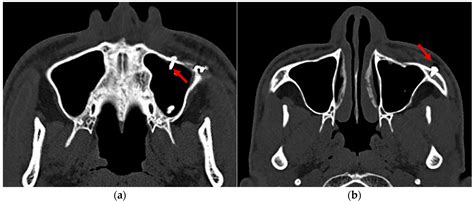

The results of a Mxailliary Sinus CT scan are interpreted by a radiologist, who will look for signs of:

• Inflammation: Swelling or infection in the sinuses.

• Obstruction: Blockages in the sinus passages.

• Abnormal Growths: Polyps, tumors, or other growths.

• Structural Issues: Deviated septum or other structural abnormalities.

Common Findings in a Mxailliary Sinus CT Scan

Some common findings in a Mxailliary Sinus CT scan include:

• Sinusitis: Inflammation of the sinuses, often due to infection.

• Nasal Polyps: Benign growths in the nasal passages.

• Tumors: Abnormal growths that may be benign or malignant.

• Fractures: Bone fractures in the sinus area, often due to trauma.

• Deviated Septum: A misaligned nasal septum that can cause obstruction.